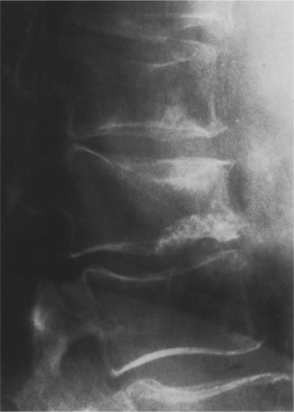

Figure 24-3 Postmenopausal osteoporosis in a 59-year-old woman. Lateral view of the thoracolumbar spine sows protrusion of disc material through a weakened end plate (Schmorl’s node). Note also the biconcave appearance of several vertebral bodies. (From Grainger: RG: Grainger & Allison’s diagnostic radiology: a textbook of medical imaging, ed 4, Philadelphia, 2001, Churchill Livingstone.)

Vertebral compression fractures (VCFs) are the most common osteoporosis-related spinal fractures presenting with clinical symptoms of back pain, posture change, loss of height, functional impairment, disability, and diminished quality of life (Fig. 24-4). These can occur without injury or fall when the bone becomes so porous or weak and it begins to compress (see the section on Fractures in Chapter 27). By age 90 years, the force required to produce failure of the L3 vertebrae is approximately one-fourth the compressive failure force at age 30 years.55

The prevalence of vertebral fractures increases steadily with age, ranging between 20% for 50-year-old postmenopausal women and 64% for older women. The majority of vertebral fractures are not connected with severe trauma, and only one in three is diagnosed clinically. Almost 20% of women will experience another fracture within 1 year after a vertebral fracture.38

Fractures are usually diagnosed by radiograph examination (x-ray) that demonstrates the fracture (Fig. 24-5) and also reveals the osteopenia leading to the diagnosis of osteoporosis. Once osteopenia is noted, other causes of metabolic bone disease must be ruled out, including hyperthyroidism, hyperparathyroidism, osteomalacia, testicular failure, malignancies, and so on. Diagnostic criteria for men with this condition are at present based on those for women, although the validity of this approach is under discussion.131 Histologically, a thinning of cortical bone and a reduction in the number and size of the trabeculae of cancellous bone occurs (see Fig. 24-1). Thirty percent or greater bone density loss must occur before such abnormalities can be noted on an x-ray film.